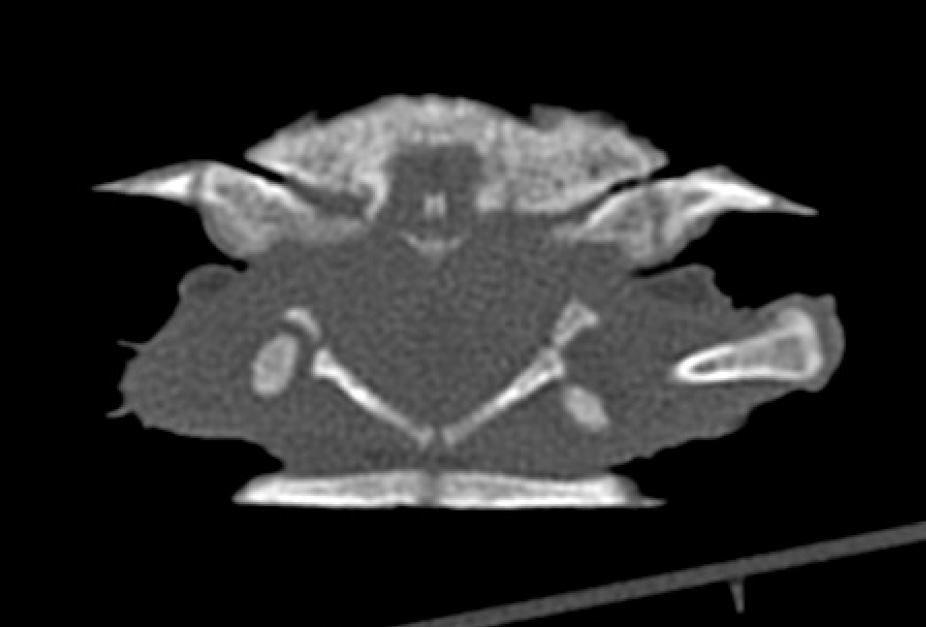

На дорсальных рентгенограммах определялось вероятное вентральное смещение головки бедренной кости из вертлужной впадины. Для подтверждения диагноза «вентральный вывих головки бедренной кости» животному провели компьютерную томографию. Данная процедура была проведена на аппарате Philips MX 16. Сканирование было выполнено в краниокаудальном направлении в положении пациента лежа на пластроне, животное было помещено в закрытый пластиковый бокс 200 × 10 мм, анестезия при исследовании не применялась. Параметры КТ: время вращения трубки 0,6 сек., 134 mAs, 120 kV, поле зрения 180 мм, размер матрицы 1024 × 1024, костное окно. Были выполнены мультипланарные реконструкции в аксиальной, дорсальной и сагиттальной плоскостях в костном окне. По результатам КТ было подтверждено вентральное смещение (вывих) головки правой бедренной кости из вертлужной впадины (фото 1, 2).